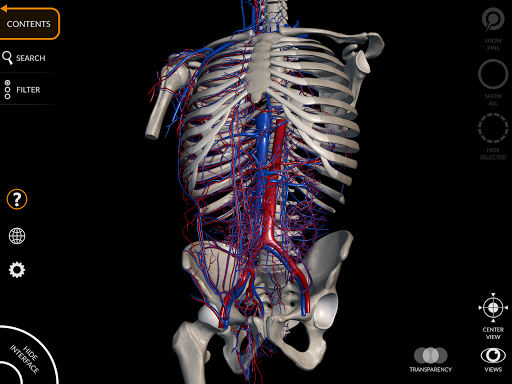

"Anatomy 3D Atlas" memungkinkan Anda mempelajari anatomi manusia dengan cara yang mudah dan interaktif.

Melalui antarmuka yang sederhana dan intuitif, Anda dapat mengamati setiap struktur anatomi dari sudut mana pun.

Model 3D anatomi sangat terperinci dan memiliki tekstur hingga resolusi 4k.

• Sistem kardiovaskular • Sistem

saraf • Sistem pernapasan • Sistem pencernaan • Sistem urogenital (pria dan wanita) • Sistem endokrin • Sistem limfatik • Sistem mata dan telinga FITUR • Antarmuka yang sederhana dan intuitif • Putar dan perbesar setiap model dalam ruang 3D • Opsi untuk menyembunyikan atau mengisolasi satu atau beberapa model yang dipilih • Filter untuk menyembunyikan atau menampilkan setiap sistem • Fungsi pencarian untuk menemukan setiap bagian anatomi dengan mudah • Fungsi penanda untuk menyimpan tampilan khusus • Rotasi cerdas yang menggerakkan pusat rotasi secara otomatis • Fungsi transparansi • Visualisasi otot melalui tingkat lapisan dari yang superfisial hingga yang terdalam • Dengan memilih model atau pin, istilah anatomi terkait akan muncul • Deskripsi otot: asal, • Tampilkan/ Sembunyikan antarmuka UI (sangat berguna dengan layar kecil) MULTIBAHASA • Istilah anatomi dan antarmuka pengguna tersedia dalam 11 bahasa: Latin, Inggris, Prancis, Jerman, Italia, Portugis, Turki, Rusia, Spanyol, Mandarin, Jepang, dan Korea • Istilah anatomi dapat ditampilkan dalam dua bahasa secara bersamaan PERSYARATAN SISTEM • Android 8.0 atau yang lebih baru, perangkat dengan RAM minimal 3GB Reversi